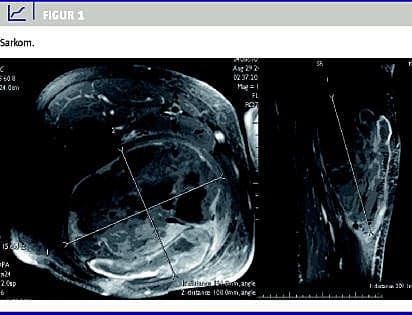

Paraklinisk: Hæmoglobin (HGB) 5,6 mmol/l, leukocytter 15,8 mia/l, C-reaktivt protein (CRP) > 270 (0-10) mg/l, glukose 12,3, glykeret hæmoglobin (HbA1C ) 11,0. Akut ultralydsskanning (UL) af højre femur viste et 10 × 10 × 20 cm intramuskulært hæmatom under organisering. Ved primær kirurgisk intervention på mistanke om absces fandtes en stor subfacial tumor. Røntgen af thorax viste et metastasesuspekt rundinfiltrat på højre lunge. Computertomografi viste metastaser til lunger og mediastinum. Helkrops-positronemissionstomografi viste tumorprocess posteriort på højre femur og bekræftede rundinfiltrat på lunge. På magnetisk resonans (MR)- skanning observeredes en intramuskulær tumor på 11 × 13 × 20 cm, som medinddrog hele bagerste muskelgruppe med nekrotiske områder, der var suspekte for malignitet (Figur 1 ). Patienten blev overflyttet til kirurgisk excision og efterfølgende kemoterapi. Den histologiske diagnose var forenelig med sarkom. Sygdommen progredierede, og patienten gik ad mortem 18 måneder efter det primære traume.